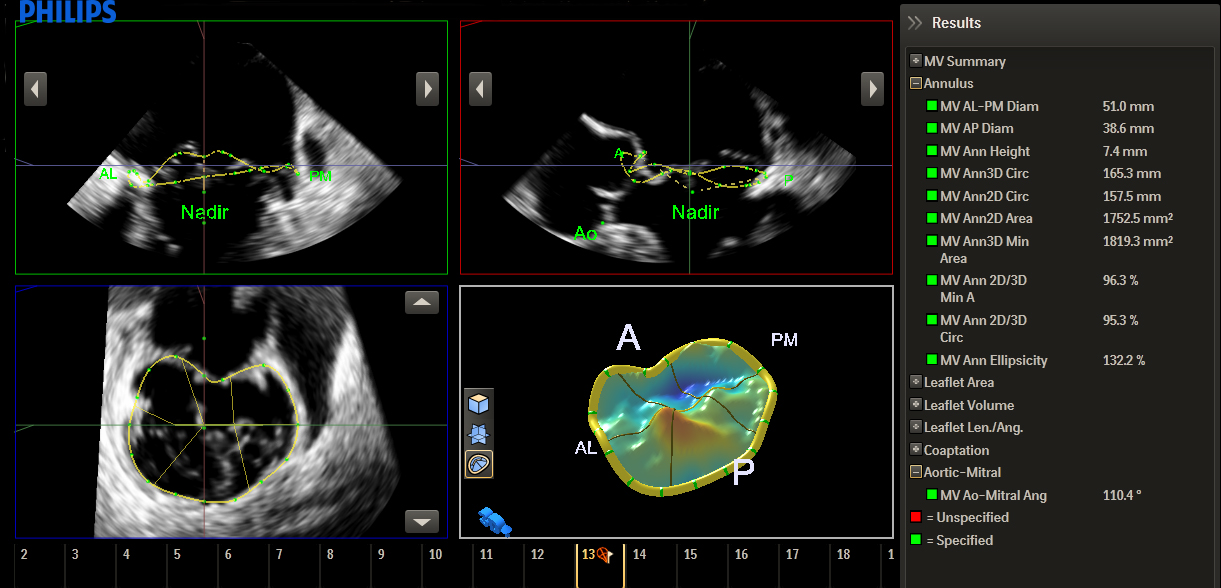

Découvrez HeartModelᴬ⋅ᴵ⋅, une nouvelle application d’intelligence anatomique appliquée à l’échographie (AIUS) intégrant les fonctionnalités suivantes pour l’échocardiographie : quantification 3D temps réel, affichages 2D automatisés et reproductibilité performante. HeartModelᴬ⋅ᴵ⋅ détecte, segmente et quantifie automatiquement l’oreillette gauche et le ventricule gauche à partir d’un volume 3D.

Cette étude a comparé la quantification entre la 2D et HeartModelᴬ⋅ᴵ⋅ 3D temps réel : HeartModelᴬ⋅ᴵ⋅ offre un gain de temps de 82 % lors de l’utilisation de la fonctionnalité d’automatisation et de 63 % lorsque des modifications mineures sont nécessaires.

Une augmentation de la reproductibilité en moins d’étapes et moins de temps que les méthodes classiques peut augmenter la fiabilité du diagnostic pour davantage d’utilisateurs.